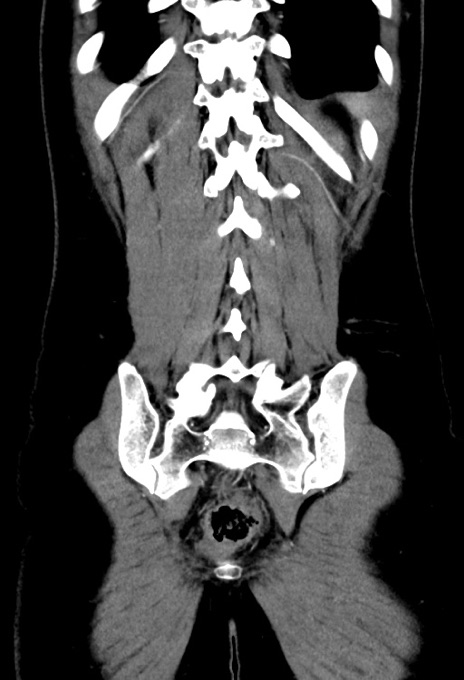

横断像